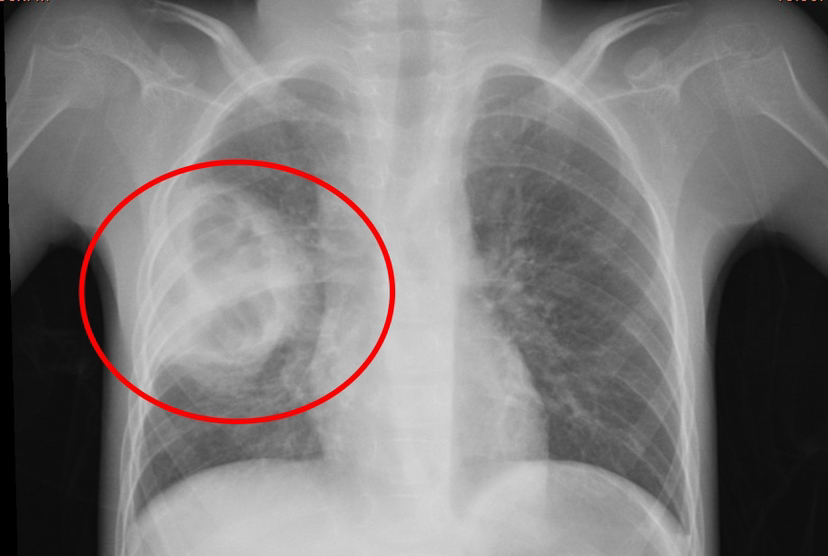

患兒小小,患有腦癱與藥物難治性癲癇,重度營(yíng)養(yǎng)不良,7歲體重僅10公斤,因長(zhǎng)期臥床導(dǎo)致肺部感染并發(fā)肺膿腫,入院時(shí)情況極為復(fù)雜,胸部CT顯示肺膿腫、肺炎合并胸腔積液,高熱不退、呼吸困難,驚厥頻發(fā),治療難度極大,家屬幾近絕望,甚至動(dòng)過(guò)放棄治療的念頭。